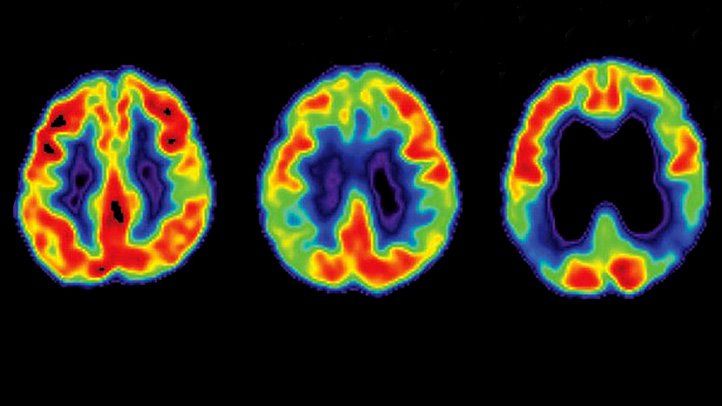

Cholinergic dysfunction often precedes widespread plaque and tangle formation, suggesting it’s an early event in Alzheimer’s. Functional imaging (e.g., PET scans) shows reduced cholinergic activity in mild cognitive impairment (MCI), a precursor to Alzheimer’s, highlighting its role in the disease’s onset.